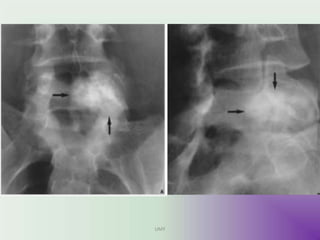

ANJALI ,20F,ABC

Rx-Curettage+ G Bone grafting

PRE OP IMMEDIATE POST OP FOLLOW UP